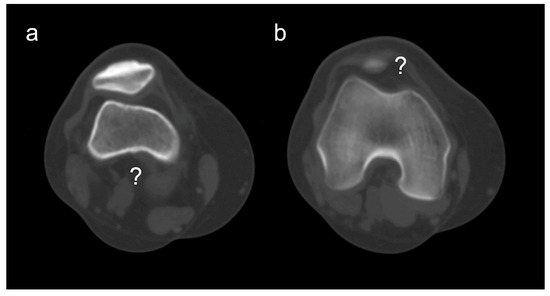

Poor Prognostic Factors in Surgically Treated Habitual Patellar Dislocation in Children and Adolescents

Background/Objectives: Habitual patellar dislocation is a rare but debilitating form of patellofemoral instability in children and adolescents, frequently associated with underlying anatomical abnormalities and ligamentous laxity. Despite multiple surgical techniques, recurrence and suboptimal functional recovery remain concerns. This study aimed to identify the [...] Read more.

Background/Objectives: Habitual patellar dislocation is a rare but debilitating form of patellofemoral instability in children and adolescents, frequently associated with underlying anatomical abnormalities and ligamentous laxity. Despite multiple surgical techniques, recurrence and suboptimal functional recovery remain concerns. This study aimed to identify the demographic, clinical, and imaging factors associated with postoperative recurrence and poorer functional outcomes in pediatric patients surgically treated for habitual patellar dislocation. Methods: A retrospective cohort study was conducted on pediatric patients treated between 2016 and 2024 for habitual patellar dislocation. Inclusion criteria required age ≤ 18 years, a minimum 12-month follow-up, and complete imaging documentation. Clinical evaluation included the Beighton hyperlaxity score, lower-limb alignment, and Lysholm Knee Score. Imaging parameters assessed patellar height (Caton–Deschamps Index), trochlear dysplasia, patellar tilt, patellar subluxation, genu valgum, and tibial tubercle–trochlear groove (TT–TG) distance. Surgical treatment consisted of individualized combinations of soft-tissue realignment, quadriceps lengthening, Roux–Goldthwait procedures, and MPFL reconstruction. Statistical analyses evaluated predictors of recurrence and postoperative Lysholm score. Results: Thirty-four patients (45 knees; mean age 12 years; 73.5% female) were included. Preoperative Lysholm scores improved from a mean of 73 to 94 postoperatively (p < 0.0001). Recurrence occurred in 32.35% of patients and was significantly associated with generalized hyperlaxity (p = 0.0041), trochlear dysplasia (p = 0.045), and lateral patellar subluxation (p = 0.039). Suboptimal postoperative Lysholm scores (<85) were observed in 11.76% of patients, all with recurrence, and were significantly associated with genu valgum (p = 0.0011) and patella alta (p = 0.036). No significant associations were found for rotational deformities or femoral condyle hypoplasia. Conclusions: Habitual patellar dislocation in children is multifactorial, and the likelihood of recurrence increases with cumulative risk factors such as hyperlaxity, trochlear dysplasia, lateral subluxation, patella alta, and genu valgum. Comprehensive preoperative assessment is essential to guide combined, individualized surgical strategies that optimize stability and functional recovery. No single technique is universally curative; rather, tailored multimodal approaches yield the most favorable outcomes. Full article

Show Figures

Figure 1